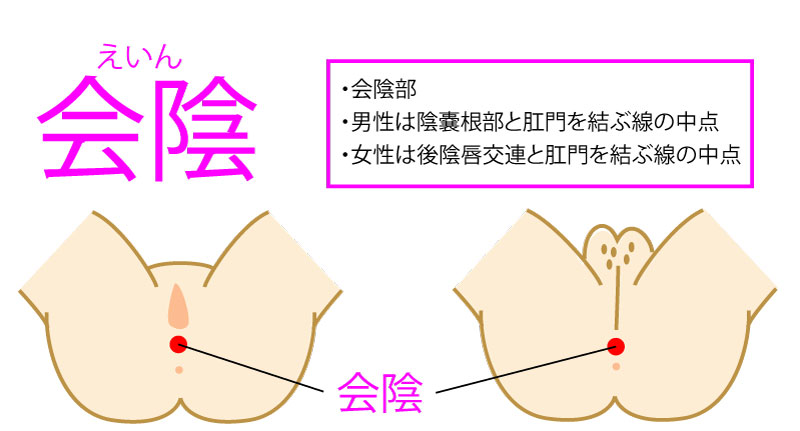

会陰 えいん は 腟口 ちつこう から肛門までを指します。 生殖器は発生学的由来により内生殖器と外生殖器に分けられます。外陰部は体表の皮膚が変化して生じた外生殖器で、外からの刺激に対して生殖器を守る役割があります。会陰部に近いほど男性化不全の程度が強い 4.陰嚢の形成は? 低形成、二分陰嚢の有無 <Quigley分類> 完全男性型 完全女性型 図:たのしく学ぶ小児内分泌より 外陰部の診察:女児の男性化 1.陰核の大きさは? 横径を計測することが多い。 >7 mm → 陰核肥大 2.膣口は確認できるか? 3.陰唇動画あり出張オイルリンパマッサージの四ツ目本舗は東京都心部のホテル・自宅へ、深夜1時迄、出張オイルリンパマッサージを提供。「no sokeibu, no life紙パンツを捨てよう!」当店の「鼠径部(そけい部)オイルリンパマッサージ」の「会陰部について」の説明

会陰 ( えいん )とは、 解剖学 において、狭義では 外陰部 と 肛門 の間、広義では左右の 大腿 と 臀部 で囲まれる 骨盤 の出口全体をさす。 恥骨結合 と左右の 坐骨結節 、 尾骨 を結ぶ菱形部となる。会陰と残尿感の解消には、 一体どのような関係性があるのでしょうか。 男性は蟻の門渡りを押すことで残尿感を解消できるのか? 排尿を終えた直後なのに「まだ膀胱内に尿が残っているような気がする、 なんだかスッキリしない」という不快感を覚える 男性の陰部のかゆみの原因として考えられる疾患とは? 男性の陰部にかゆみの症状があるとき、大まかな原因としては「性感染症」「皮膚疾患」の2つの場合が考えられます。 かゆみのある性感染症としては「性器ヘルペス・尖圭コンジローマ・梅毒」などがあり、どれも性行為により感染する可能性があります。 性器ヘルペスでは、陰部に水膨れができ

会陰部 広義の会陰の定義 (会陰部も参照) 前方の陰丘、外側の大腿内側面、後方の殿溝と殿間裂の上縁に挟まれた菱形の領域 (M) 狭義の会陰の定義 男性の場合尿道と会陰の間、女性の場合膣と肛門の間を指す (KH237) WordNet the general region between the anus and the男性の会陰は前後径5~6センチメートル、女性では2~3センチメートルである。 この部分の皮膚の正中線には色素に富んだ会陰縫線 (ほうせん)があり、男性では陰嚢縫線に続く。 会陰部皮下には脂肪組織、平滑筋線維が多く存在し、その深部には横紋筋からなる会陰筋層がある。 骨盤腔 (こう)を上方からみると、骨盤下口を会陰筋が筋膜、腱膜 (けんまく)とともに会陰部のヘルニアについて情報をまとめました。 ヘルニア治療辞典 男性と女性では、起こる場所が異なると言われていますが、女性の方がかかる率が高くなっています。 恐らく、女性は妊娠や出産などがあるため、会陰部が大きく収縮することが原因の1つではないかと考えられます。

会陰 えいん Cv1